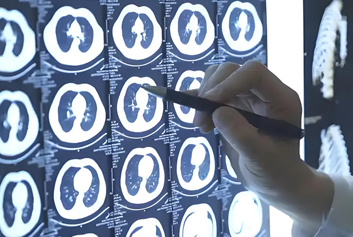

云影像/云胶片迈德卫医疗影像云-未来已来:医疗科技的奇妙变革在这个科技日新月异的时代,医疗领域正经历着前所未有的变革。未来医疗科技,宛如一把神奇的钥匙,正逐渐开启一扇通往全新健康世界的大门,它所带来的改变,将深刻影响我们每一个人的生活。跟着云影像/云胶片迈德卫医疗影像云一起探索下未来医疗的发展!先从疾病诊断说起,以往去医院看病,各种繁琐的检查、漫长的等待结果...

云胶片/电子胶片迈德卫云影像-告别胶片堆!医疗影像迈入无胶片时代,改变的不只是一张片子医生,我的CT片好像落在上次检查的科室了.在过去的医院影像科,这样的对话几乎每天都在上演。患者抱着一沓厚重的胶片奔波于各个诊室,医生在昏暗的读片灯下反复调整角度,护士则要花费大量时间整理、归档堆积如山的胶片-这是传统医疗影像模式下,医患双方共同的痛点记忆。而如今,随着数字化技术的深度渗透,医疗影像已...